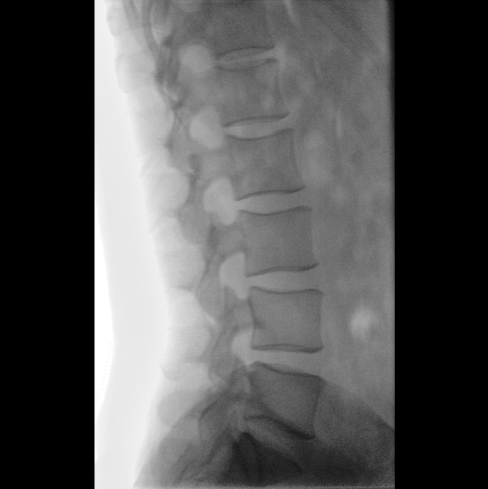

平板尺寸升級 呈現(xiàn)更多解剖細節(jié)

采用30CM×30CM大尺寸動態(tài)平板探測器,成像面積較傳統(tǒng)平板探測器大幅提升。

圖像清晰細膩

高清像素,低信噪比,細小的組織結構也可以清晰顯示。

Clinical picture